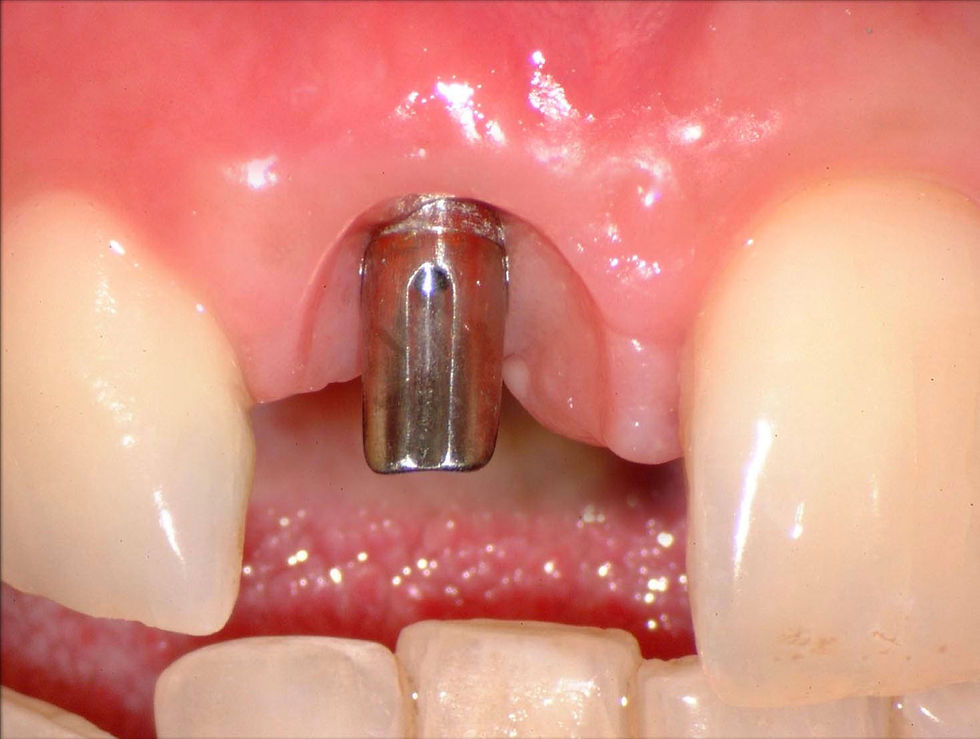

The regeneration of hard and soft tissues keeps peri-implant volumes unchanged over time.

The control at 6 months shows the maintenance of horizontal volumes.

Control image at 6 months from implant insertion, showing an ideal adaptation of the gingival parabola thanks to the management of the soft tissues through a series of temporary crowns.